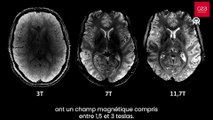

Fransa Atom Enerjisi ve Alternatif Enerjiler Kurumu (CEA), dünyanın en güçlü manyetik rezonans görüntüleme (MRI) cihazıyla elde edilen, insan beyninin en net görüntüsünü yayınladı.